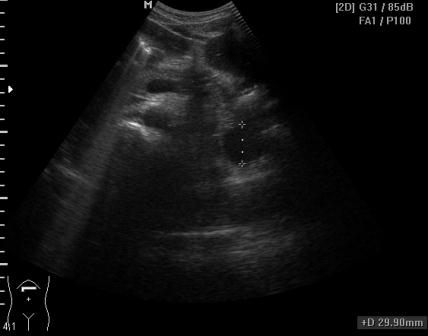

Женщина, 31 год, с умеренной болью в эпигастрии. Беспокоит боль периодически в течение 2 месяцев, усилилась примерно 2 недели назад. ОАК, ОАМ, БАК в норме, температура тела в норме. В малом тазу большое кол-во жидкости мелкодисперстной, особенно кпереди от матки (не сохранила ни скан, ни видео).

в малом тазу жидкость мелкодисперстная

Из того, что понятно: есть киста хвоста поджелудочной железы, жидкость в малом тазу (мелкодисперстная) и немного в брюшной полости (с нитями фибрина), кисты правого яичника.

P.S.:Результат повторного кульдоцентеза: амилаза 817, эритроциты в большом количестве.

Геморрагическая жидкость характерна для о.панкреатита.